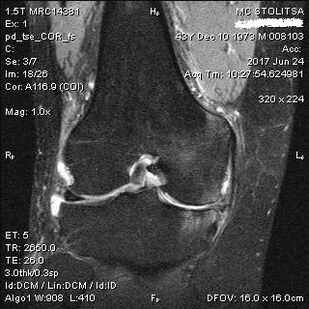

Tizlar bo'g'imlarining artrozligi dimomatolog yoki ortopedining idorasida amalga oshiriladi. Doktor ta'sirlangan qo'shma, palplaydi, shikoyatlarni tinglaydi, qo'shimcha savollarni beradi. Bir nechta testlarni bajaradi - masalan, bemordan oyog'ini egishni yoki bir necha qadam yurishni so'rash. Keyin, kasallikning bosqichi yoki patologik o'zgarishlarning xususiyatini aniqlashtirish kerak bo'lsa, u sizga qo'shimcha tadqiqotlar uchun murojaat qiladi. Masalan, kompyuter tomografiyasi yoki rentgenografiyasi uchun.